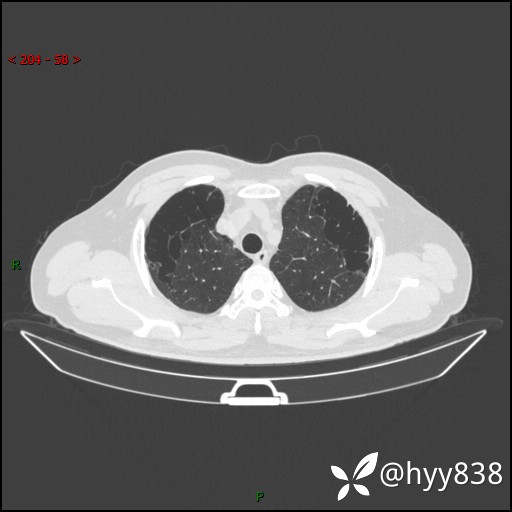

一周前胸部CT